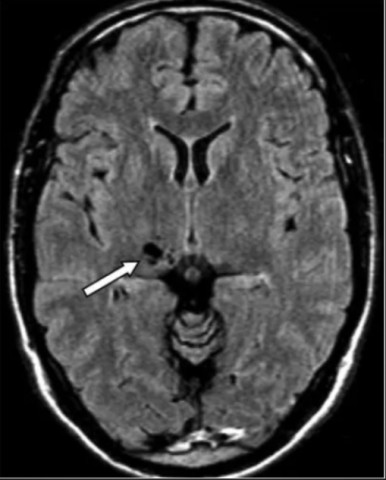

Периваскулярные пространства отвечают за циркуляцию спинномозговой жидкости, которая производит очистку мозга от побочных продуктов метаболизма во время глубокого сна. Увеличение этих пространств происходит при старении, а также связано с развитием деменции. Однако сравнивая МРТ-снимки испытуемых астронавтов, учёные не обнаружили изменений у ветеранов космического полёта. Старший автор исследования Хуан Пьянтино, доктор медицинских наук, доцент неврологии в Медицинской школе OHSU, описал эту странность гомеостазом — стремлением нашего организма к постоянству внутренней среды.

Периваскулярные пространства